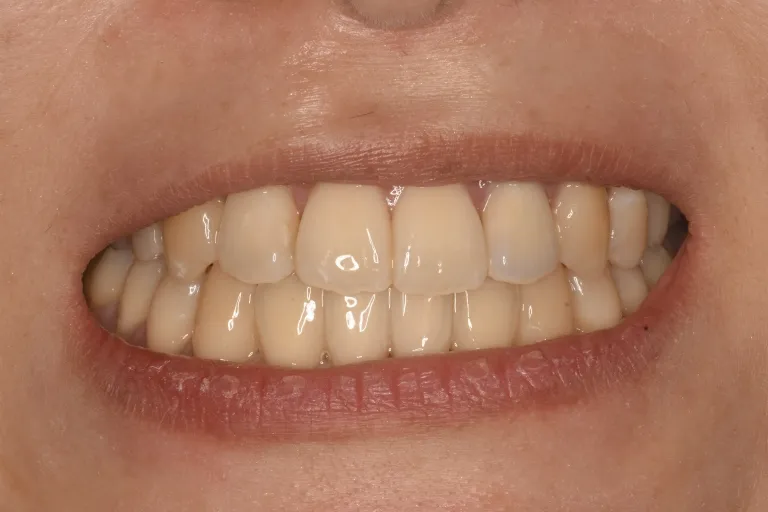

• 治療後 前歯が閉じて、しっかり噛めるようになりました

治療後 前歯が閉じて、しっかり噛めるようになりました

マウスピース矯正とインプラントアンカーを併用することで手術なしで開咬の改善を行いました。

患者さんの感想 手術をせずに噛み合わせが良くなり、前歯で噛み切れるようになって食べるのが今までよりも楽しくなりました。前歯が当たるようになり滑舌もよくなったと周りから言われるようにもなりました。マウスピース矯正でこんなに早く治ると思わなかったので、もっと早くから治療すればよかったです。マウスピース矯正中は間食ができないのが辛かったですが、健康的には良いとだろうとポジティブに捉えて頑張ることができましたし、矯正をしてから周りから顔が小さくなったと言われるようになりました。矯正治療中のゴムかけ最初は大変でしたが、頑張った甲斐がありました。